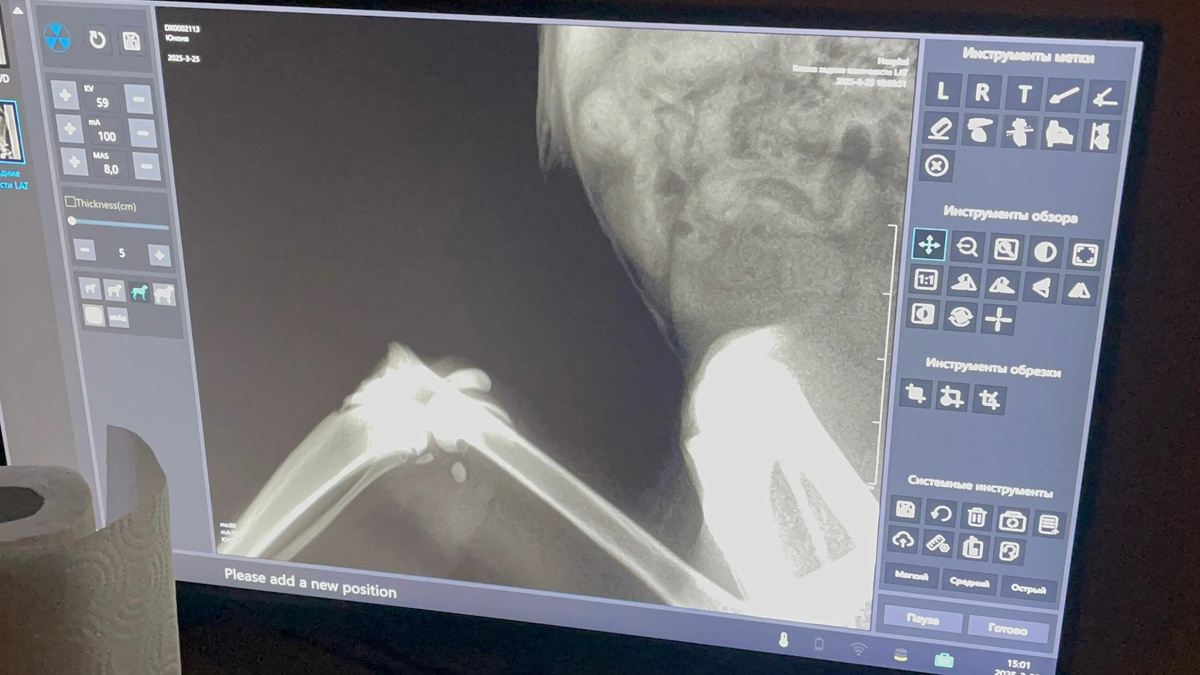

Очень ухоженная, красивая, нежная и ласковая кошечка. Сделали рентген... без комментариев...

Когда врач стал оперировать колено, он под наркозом сделал ещё один снимок и выяснилось, что у Юноны три пер'елома: бедро, колено и таз! Такое впечатление, что по ней проехалась машина! Вот до чего доводит самовыгул!